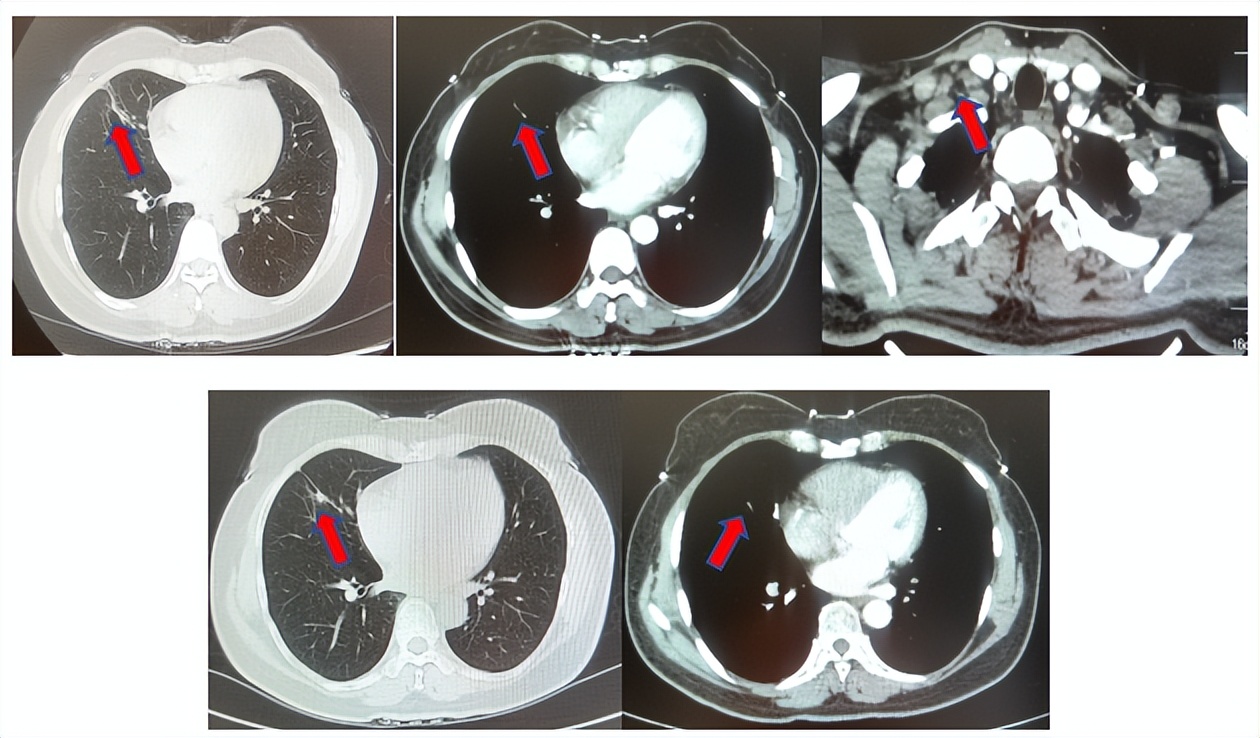

2.2影像学检查(图5)

肺+全腹CT增强:右肺中叶肿块,考虑恶性,双肺胸膜下炎症,双侧胸膜局限性增厚,右侧锁骨上淋巴结增大,纵隔淋巴结稍大;

颈部CT增强:右侧锁骨上及右颈部、纵隔多发淋巴结肿大。

脑MRI增强:头MR平扫+增强未见确切异常。

图5:上两图分别展示基线时肺CT肺窗及纵隔窗右肺中叶病灶影像,下两图表示基线状态时纵隔淋巴结及锁骨上淋巴结影像。

患者符合我科正在开展的一项“评估信迪利单抗或安慰剂联合培美曲塞和铂类化疗用于晚期或复发性肺鳞状细胞非小细胞肺癌一线治疗有效性和安全性的随机,双盲,III期研究(ORIENT-11)”临床研究入组条件,应用信迪利单抗或安慰剂联合培美曲塞+卡铂治疗4周期,信迪利单抗或安慰剂联合培美曲塞维持治疗13周期,后应用信迪利单抗或安慰剂应用至2年。试验结束后出组,揭盲患者为信迪利治疗组。治疗期间最佳疗效肺内病灶近CR(图6)。停药后每3个月-6个月复查随访,未见肿瘤复发转移征象(图6),截止至目前为止,一线无进展生存已超过75个月。

图6:上三图分别展示2019年6月患者达到最佳疗效时肺CT肺窗及纵隔窗右肺中叶病灶及锁骨上淋巴结影像,下两图表示2025年2月患者最近复查评效时肺CT肺窗及纵隔窗肺内病灶影像